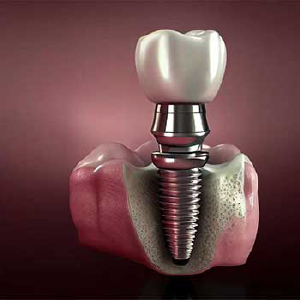

ریشههای تیتانیومی با دقت بالا جایگزین دندانهای از دسترفته میشوند و با اتصال محکم به استخوان فک، جویدن مطمئن، گفتار واضح و زیبایی طبیعی لبخند را بازمیگردانند.

دراین روش با قرار دادن چهار تا شش ایمپلنت در هر فک، پروتز ثابت کامل با استحکام بالا مهار میشود و عملکرد طبیعی و لبخندی پایدار را فراهم میکند.